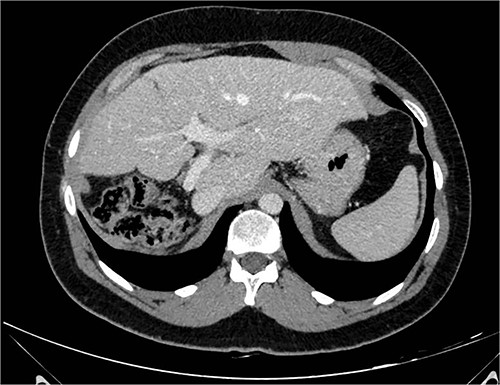

A 26-year-old, previously healthy man was admitted in March 2019 to the Surgical Department of our Hospital with abdominal distension and discomfort in the last 6 months. On physical examination, a palpable large mass was documented in the right hypochondrium extending below the umbilicus with tenderness in the upper abdomen without evidence of ascites. His medical history was little significant, just fraternal twin and hypothyroidism. Laboratory tests were carried out but tumour markers, hepatitis virus markers, and liver enzymes were normal and not diagnostic. Contrast enhanced CT-scan highlighted a giant, hypodense, heterogeneous, solid lesion without cystic component in the right lobe of the liver (Fig. 1). The tumour compressed neighbouring parenchyma and displaced abdominal organs and the retro-hepatic vena cava was also compressed with the middle hepatic vein slightly occluded by thrombotic material. Percutaneous needle biopsies were performed in different areas of the mass. All samples showed mesenchymal tissue with low proliferative index MIB1, and the pathologist suggested diagnosis of MHL. Following a thorough review of the literature, in view of the possibility of malignant degeneration and the high rate of local recurrence, radical liver surgery was proposed. Liver volumetry was measured, and the future liver remnant appeared sufficient to avoid post-operative liver failure. For this reason, liver transplantation was ruled out in favour of right hemi-hepatectomy without segment 1, according to Brisbane classification. In April 2019, the patient was admitted in operatory room after resolution of the middle hepatic vein thrombus with anticoagulant therapy. Right hepatectomy was carried out in 330 min.

At 42 months follow-up liver function tests were normal and CT-scan performed 6 months, 1–2–3 years after surgery were negative for disease recurrence (Fig. 2).